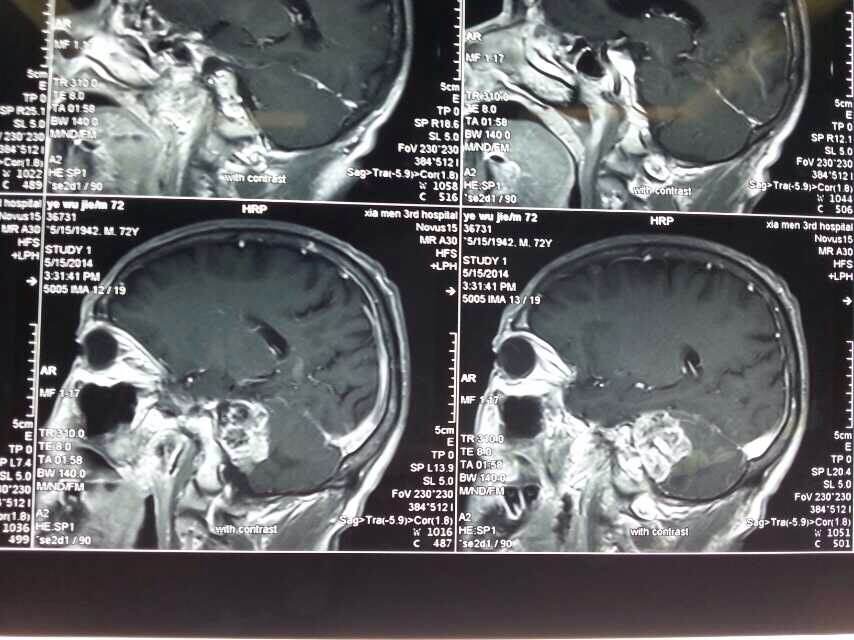

2014520是个特别的日子,第三伦理片 手术室灯火通明,神经外科调集所有的技术团队手术一台接一台,有脑动脉瘤破裂的,有脑外伤出血的,忙碌不停。